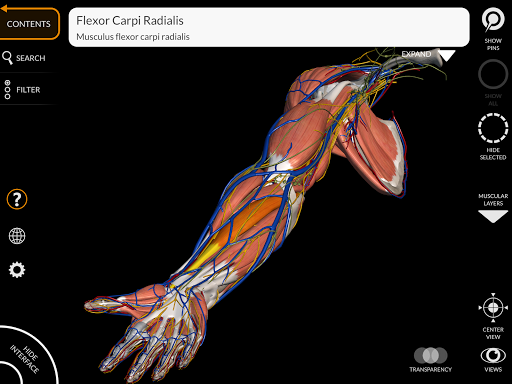

"Anatomy 3D Atlas" vous permet d'étudier l'anatomie humaine de manière simple et interactive.

Grâce à une interface simple et intuitive, il est possible d'observer chaque structure anatomique sous n'importe quel angle.

Les modèles anatomiques 3D sont particulièrement détaillés et avec des textures jusqu'à une résolution de 4k.

La subdivision par régions et les vues prédéfinies facilitent l'observation et l'étude de parties individuelles ou de groupes de systèmes et les relations entre différents organes.

MODÈLES ANATOMIQUES 3D

• Système musculo-squelettique

• Visualisation des muscles à travers des niveaux de couches depuis les plus superficielles jusqu'aux plus profondes

• Description des muscles : origine, insertion, innervation et action